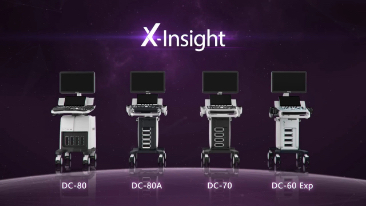

X-Insight

X-Insight is an insightful solution to envision more.

MindrayŌĆÖs brand-new solution is an excellent fusion of continuous customer insights into clinical needs, combined with continually evolving cutting-edge ultrasound technologies. Full of vitality, with the goal of insight into the future and pursuit of the infinity, it is constantly improving with increased scalability.